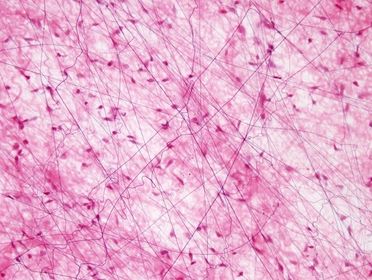

Tejido conectivo: conjuntivo (denso)

Tejido conectivo: conjuntivo (laxo)